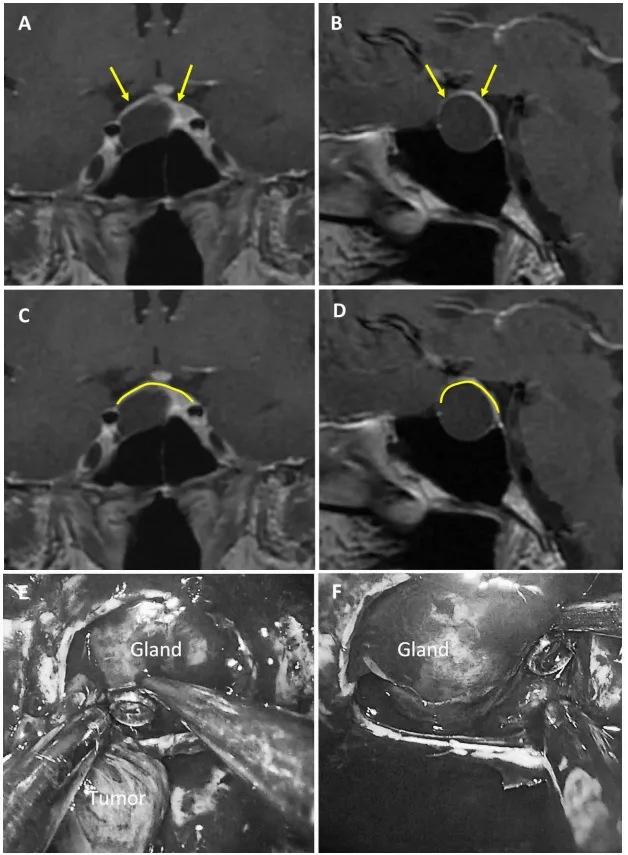

圖2:75歲女性無功能大腺瘤患者。a、b術(shù)前MRI:黃色箭頭指示厚度大于1毫米的強化屏障區(qū)。c、d術(shù)前MRI:黃色標記線標示強韌屏障位置。e、f術(shù)中圖像:可見由垂體腺構(gòu)成的屏障結(jié)構(gòu)。